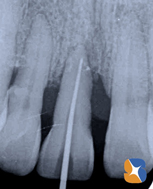

〈レントゲンの結果〉

歯周病のため、歯を支えている骨がかなり失われています。このレントゲン画像を見れば、まず「抜歯」と言われるでしょうね。本気で残すことを希望するのであるならば、歯茎の手術&再生治療(エムドゲイン)を考えます。仮にグラつきが落ち着けば、最後はセラミックで前歯をきれいに整えますか?。